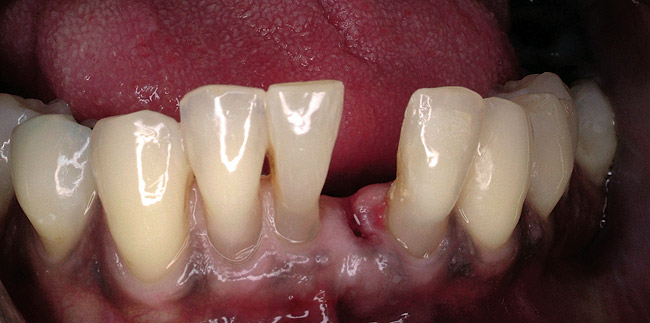

When fiber-reinforcing materials were introduced, the focus for their use was for periodontal splinting and stabilization resulting from tooth mobility.6,10,16,41-43 There is no doubt that splinting does reduce tooth mobility while the splint is in place.44 In the last decade, research supports the use of periodontal splinting as recommended therapy to stabilize those teeth to improve long-term prognosis.45-47 In a long-term clinical evaluation of splinting over a period of 48 to 96 months, using the original Ribbond Reinforcement Ribbon in fiber-reinforced composite resins was highly successful.17 The success of these splints can be attributed to close adaptation of the fiber ribbon to the tooth surface combined with cross stabilization of the mobile teeth by placing adhesive composite resin on the facial surfaces (Figure 4A, Figure 4B, Figure 4C, Figure 4D, Figure 4E).34,35 Splinting of traumatized teeth with fiber-reinforcing materials and adhesive composite resin has also been reported.48,49 When using fiber to stabilize the traumatized tooth or teeth or for tooth stabilization after re-implantation, the tooth must be allowed to have some movement and not be fixed in place.50,51